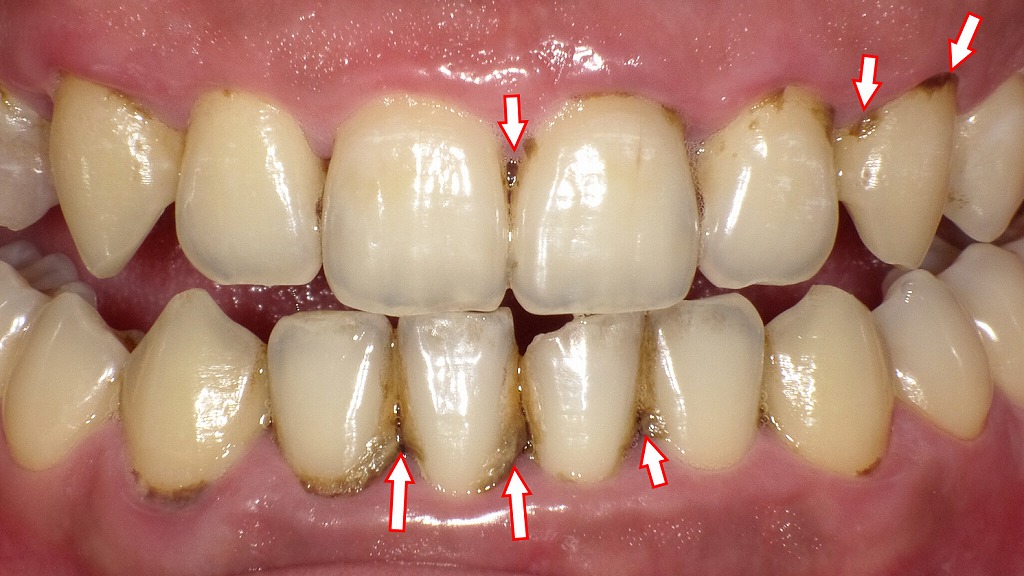

この画像は、歯の表面や歯と歯の間に黒い歯石(黒色歯石・縁上歯石)が沈着している様子を示しています。

赤い矢印の部分に注目すると、歯肉の境目や隣接面に黒〜茶色の付着物が見られます。

黒い歯石は、主に**歯肉縁下歯石(しにくえんかしせき)**と呼ばれ、歯ぐきの縁や内部にできる硬い沈着物です。

唾液中のカルシウムやリン酸が、プラーク(歯垢)に含まれる細菌と反応して石灰化したもので、時間が経つほど黒く変色します。

喫煙者や歯周病の方に特に多く見られます。

- 歯石表面はざらざらしており、細菌(プラーク)が付着しやすいため、

→ プラークの温床となり、歯周病や口臭の原因になります。 - 歯ブラシでは除去できず、放置すると炎症が進み、歯ぐきが下がったり出血しやすくなります。